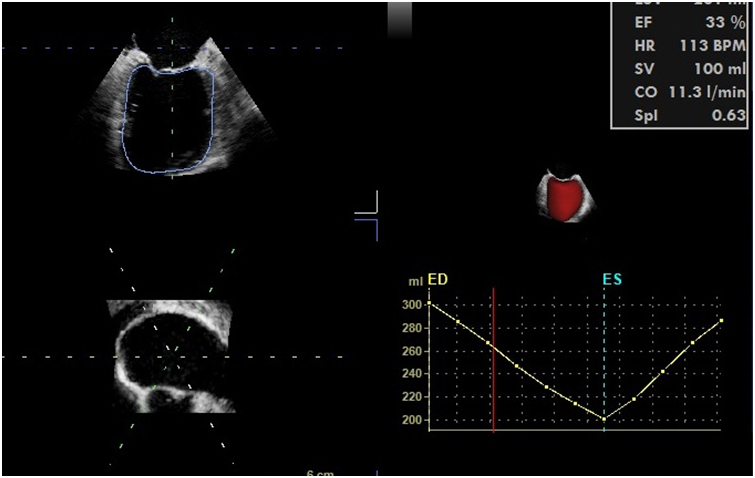

左心室有两条功能曲线(图7),容积-时间曲线和压力-时间曲线,左心室容积-时间曲线的最大值点对应着左心室舒张末容积,最小值点对应着左心室收缩末容积,最大值点和最小值点之间的差值反映每博输出量(SV)。EF(射血分数)=SV/EDV。

围手术期获得实时精确的LV容积-时间曲线尚不容易,需要用实时三维超声心动图技术、二维和三维图像自动分割技术(图8)、结合辛普森法计算得到,这种方法用在术中监测左心室的容积-时间曲线成本较高。如果心室形态正常,我们还是推荐用M型超声测量LVEDD/LVESD,计算FS(FS=LVEDD-LVESD/LVEDD)或者左心室中段短轴2D切面测量计算FAC=LVEDA-LVESA/LVEDA;EF≈2FS。

图8 3D-TEE 获得左心室容积-时间曲线